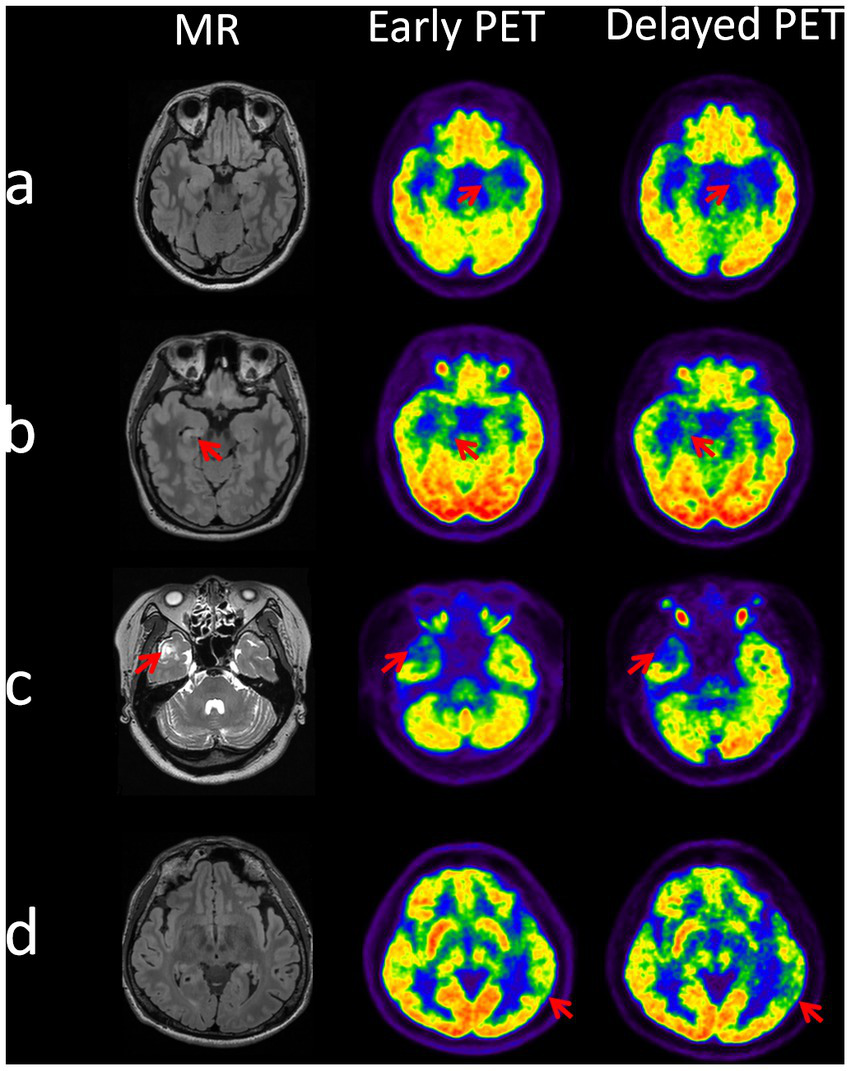

Overall, as the example shown in Figure 4, the delayed images seem to be better at potential EZ identification compared to the earlier imaging.

Figure 4

Identification of epileptogenic zones at dual time points on PET images in 4 cases. Case a (patient 6): EZ localized to the left mesial temporal lobe, two time point AIs of 14.92 (early time) and 23.64 (delayed time). Case b (patient 30): EZ localized to the right mesial temporal lobe, two time point AIs of 10.64 (early time) and 16.04 (delayed time). Case c (patient 32): EZ localized to the right lateral temporal pole, two time point AIs of 23.66 (early time) and 28.77 (delayed time). Case d (patient number 38): EZ localized to the left posterior temporal region, two time point AIs of 10.7 (early time) and 18.87 (delayed time).